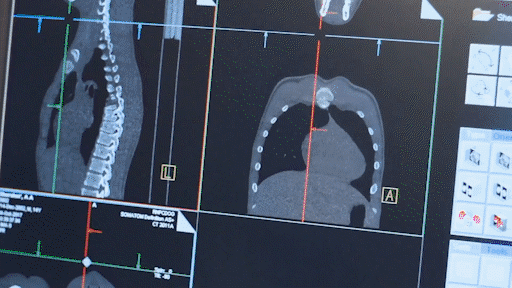

值得一提的是,公司设计研发用于特发性肺纤维化治疗的药物ISM001-055,从靶点发现到提名临床前候选化合物仅花费了270万美元研发经费,耗时仅18个月,成为首个由AI推动进入临床的创新药。